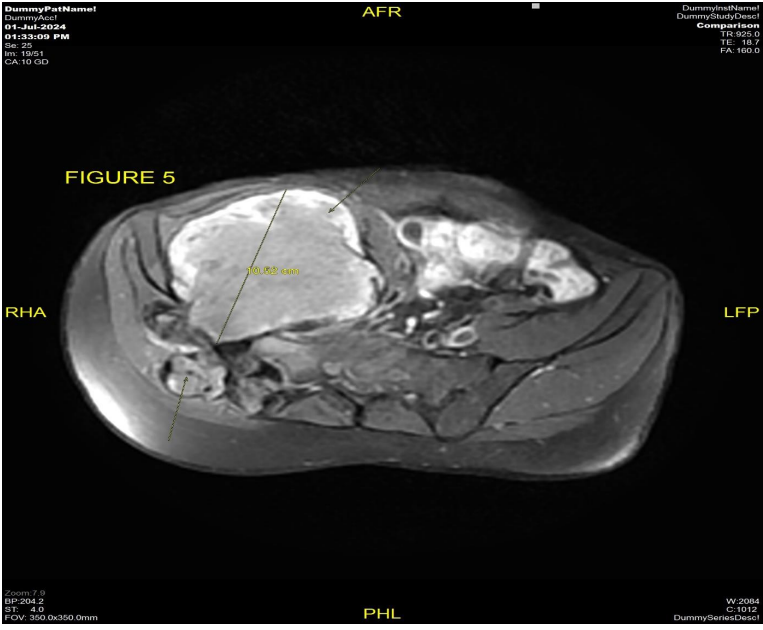

The patient underwent MRI pelvis (Fig 1 & 2) and PETCT (Fig 3 & 4) for initial evaluation (03/2024) at our institute which showed ill-defined large altered signal intensity heterogeneously enhancing mass in the right lumbar region with both intra as well as intrapelvic component by causing erosion of the right iliac bone involving the adjacent iliopsoas and gluteus muscles with central necrosis. On PET-CT scan the lesion showed significant FDG uptake with no other abnormality in the rest of the scan. Text the patient was planned for neoadjuvant chemotherapy and then for surgery. Patient took 2 cycles of neoadjuvant chemotherapy (Holoxan and Adriamycin), but after 2 cycles of chemotherapy response evaluation MRI was done (01/07/2024) (Fig 5) which showed increase in the size of lesion, so patient was planned for targeted therapy ie tyrosine kinase inhibitors, Pazopanib.

Figure 5: MRI pelvis dated 07/2024 axial view T1 post-contrast sequence shows interval increase in the size of ill-defined heterogeneously enhancing necrotic mass measuring approximately 10.5 cm in AP dimension involving the right lumbar and pelvic region causing erosion of the adjacent right iliac bone and transverse process of S1 and S2 Vertebrae with both intra as well as extrapelvic component.

Figure 5